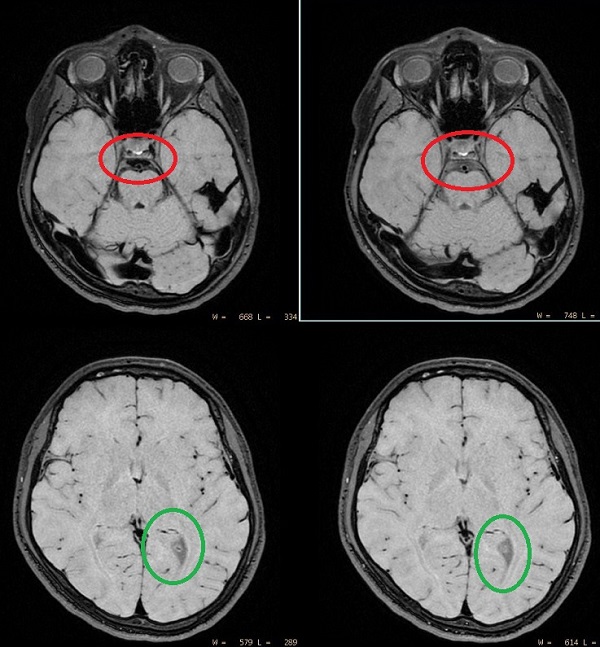

Figure 6. VEST image comparison

Table 6. Vest image comparison

Left imagesRight images

VEST=2cm/s

MSDE Direction=ALL

VEST=10cm/s

MSDE Direction=SI

Pros (+) of low VEST: Slow blood flow suppression (green)

Cons (-) of low VEST: CSF is suppressed if it flows (red)